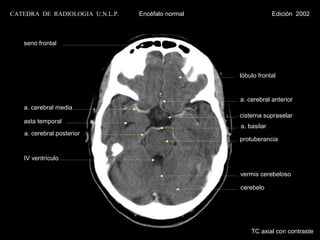

seno frontal

lóbulo frontal

a. cerebral anterior

a. cerebral media

cisterna supraselar

asta temporal

a. basilar

a. cerebral posterior

protuberancia

IV ventrículo

vermis cerebeloso

cerebelo

TC axial con contraste